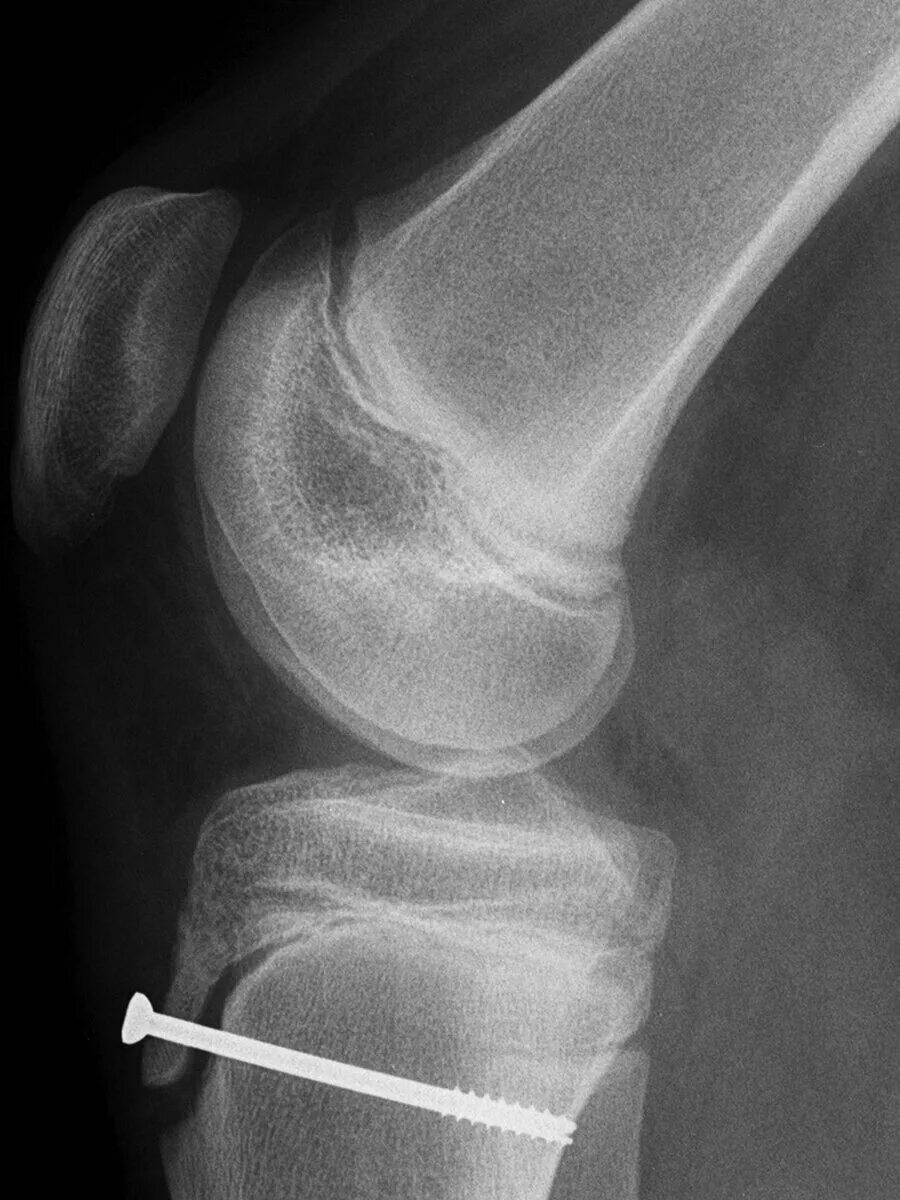

Болезнь осгут шляттера